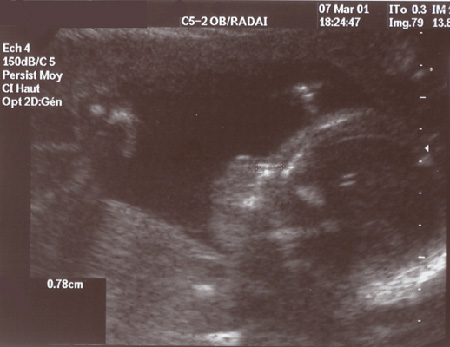

7 mars - le fémur : 39 mm !